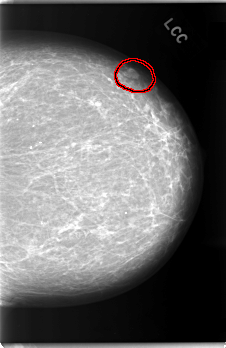

C_0084_1.LEFT_CC

LEFT_CC LINES 5904 PIXELS_PER_LINE 3832 BITS_PER_PIXEL 12 RESOLUTION 50 OVERLAY

FILE: C_0084_1.LEFT_CC.OVERLAY

TOTAL_ABNORMALITIES 1

ABNORMALITY 1

LESION_TYPE MASS SHAPE LOBULATED MARGINS CIRCUMSCRIBED

ASSESSMENT 4

SUBTLETY 5

PATHOLOGY MALIGNANT

TOTAL_OUTLINES 1

BOUNDARY